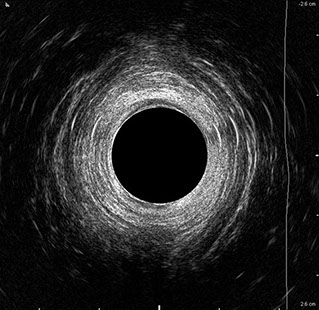

L’ecografia transanale è un esame diagnostico per immagini che consiste nell’introduzione di un trasduttore ad ultrasuoni. Le immagini qualitativamente migliori del canale anale sono ottenute usando un trasduttore rotante, montato in un manipolo rigido, che fornisce un’immagine a 360°. Con le apparecchiature più moderne è anche possibile ottenere immagini tridimensionali.

L’ecografia transanale permette di distinguere la sottomucosa che riveste il canale anale, lo sfintere anale interno, e lo sfintere anale esterno.